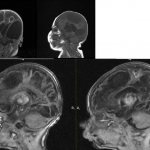

Only a qualified and experienced neurologist can differentiate the described pathology and other similar diseases. The doctor carefully examines the patient and collects a detailed history, determines the frequency of pain and all the factors that provoke it. Based on the data obtained, the diagnosis of “neuralgia” is established. To clarify the causes of the inflammatory process, the doctor may prescribe a magnetic resonance imaging of the head.